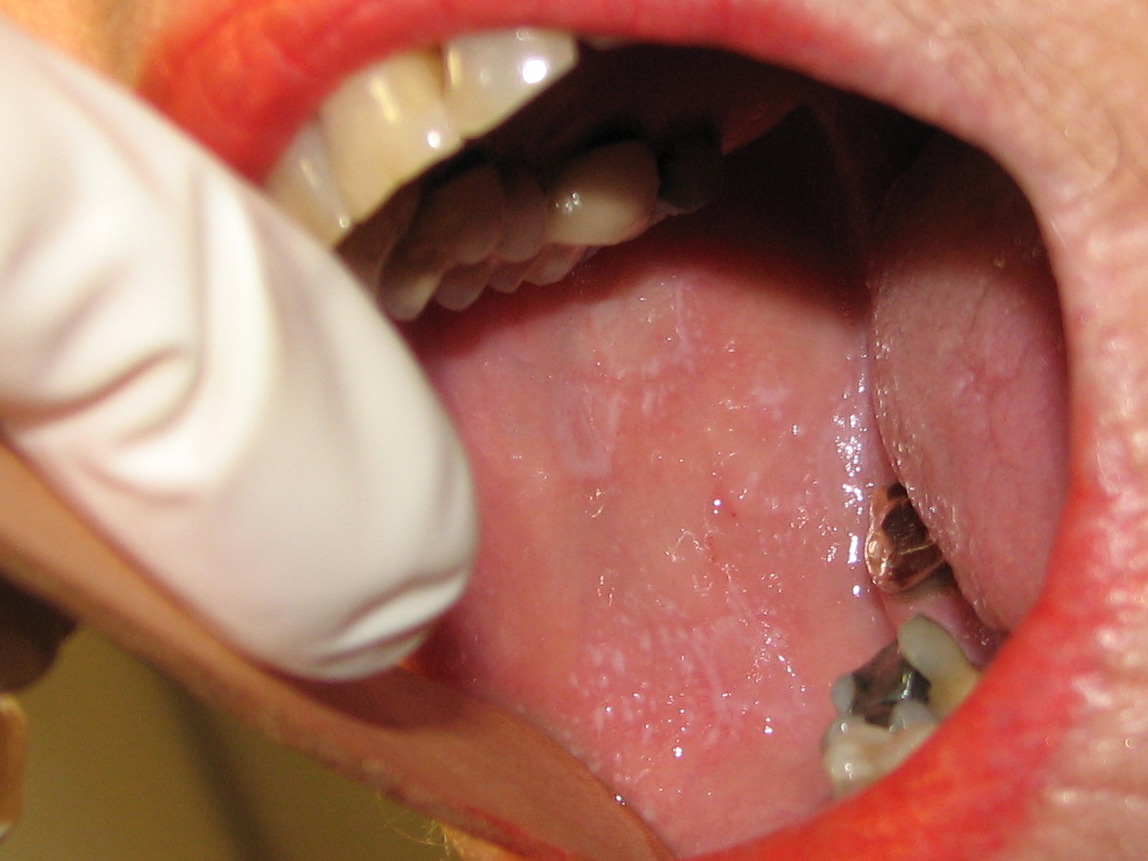

• Hvidlige maculae og striber af netagtig karakter (netmelontegning), som kan udvikle sig til mere atrofiske eller erosive områder. Kindslimhinden er hyppigst afficeret, men tungen, gingiva og læber kan også være ramt

• 15-30 % har kun slimhindeforandringer

Slimhindeforandringer ved lichen planus.

Slimhindeforandringer ved lichen planus forekommer hyppigt og karakteriseres af et netværk af hvide streger (netmelontegning).